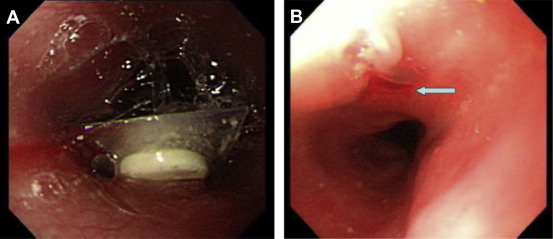

(A) A press-through-package 2cm in largest diameter with a sharp edge impacted ...

Figure 4.

(A) A press-through-package 2 cm in largest diameter with a sharp edge impacted at the upper esophagus. (B) After endoscopic removal of the package with a condom-made protection hood, mucosal ulceration was seen at the impacted site (arrow).